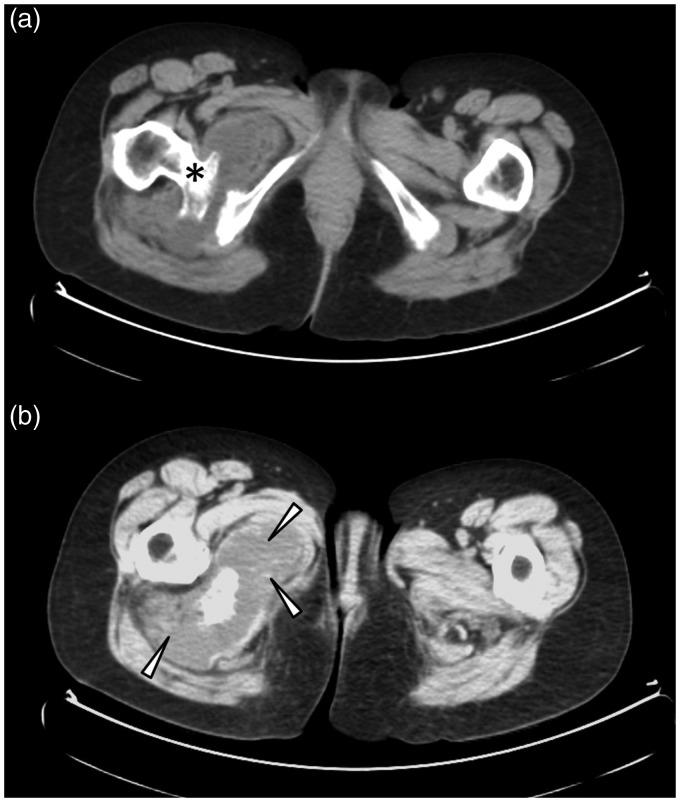

We present the case of a 53-year-old woman with a known history of hereditary multiple exostosis disease referred for further imaging work-up after ultrasound and computed tomography leading to the suspicion of malignant transformation of an osteochondroma (exostosis) located on the posteromedial aspect of the right proximal femur. Imaging examinations suggested an ischiofemoral impingement resulting in a secondary bursitis associated with the development of an internal lipoma arborescens. This rare association explained the complexity of the diagnosis. Magnetic resonance imaging (MRI) played a key role in correctly identifying this benign complication of the osteochondroma and in distinguishing those observations from a secondary exostotic chondrosarcoma. MRI findings were subsequently confirmed at surgery and pathological examination.

我们报告了一例53岁女性病例,该患者有遗传性多发性骨软骨瘤病病史。在超声和计算机断层扫描后,怀疑位于右股骨近端后内侧的骨软骨瘤(外生骨疣)发生恶变,遂进行进一步影像学检查。影像学检查提示坐骨股骨撞击,导致继发性滑囊炎,并伴有内部树状脂肪瘤的形成。这种罕见的关联解释了诊断的复杂性。磁共振成像(MRI)在正确识别骨软骨瘤的这种良性并发症以及将这些表现与继发性外生骨疣性软骨肉瘤区分开来方面发挥了关键作用。MRI结果随后在手术和病理检查中得到证实。